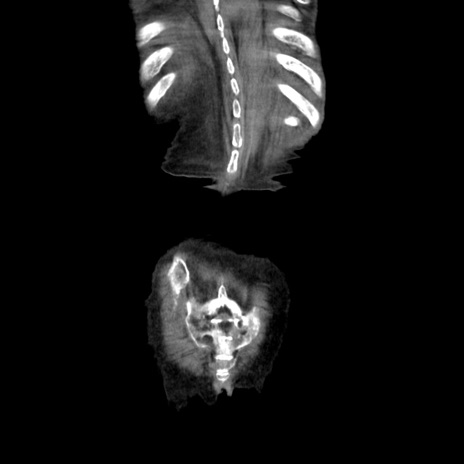

症例27(冠状断像)